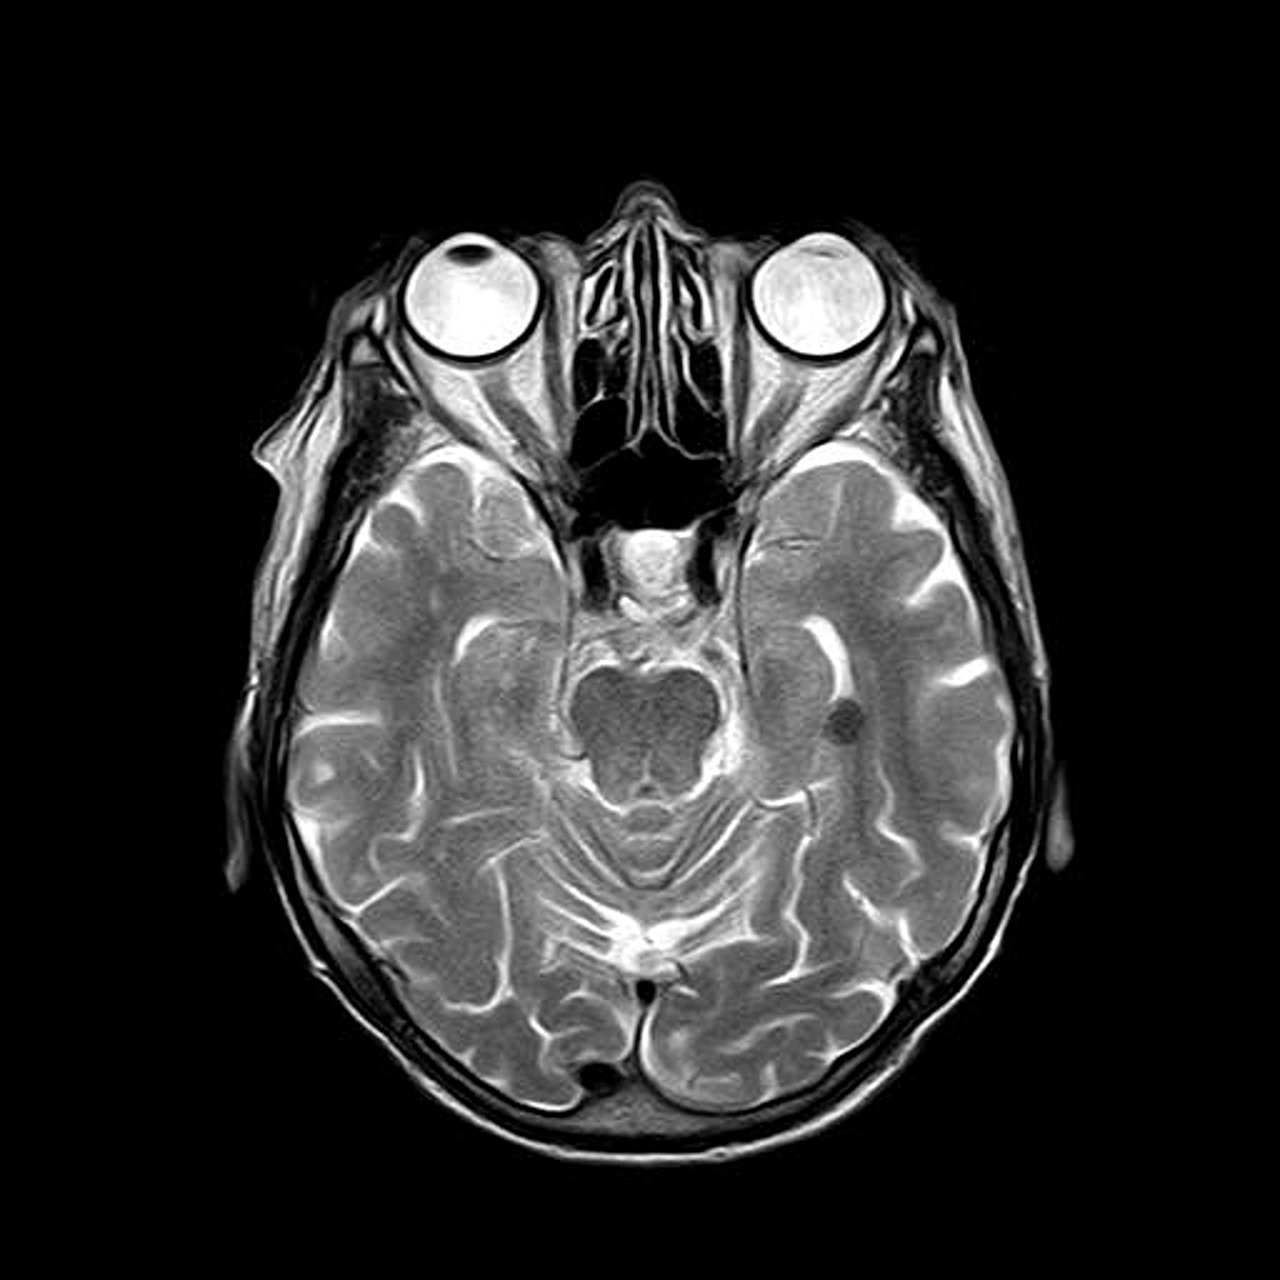

치매는 단순한 기억력 저하가 아니라 일상생활에 심각한 영향을 미치는 질환입니다. 많은 사람들이 "나는 괜찮겠지"라고 생각하지만, 치매는 조기에 발견하고 적절한 조치를 취해야 진행을 늦출 수 있습니다. 특히 초기 치매 검사는 필수입니다. 이 글에서는 치매 초기 검사가 중요한 이유와 치매를 예방하기 위한 방법을 알아보겠습니다.

치매는 완치가 어려운 질환이지만, 조기에 발견하면 진행 속도를 늦출 수 있습니다. 치료 가능한 경도인지장애(MCI) 단계에서 생활습관을 개선하고 약물 치료를 시작하면 정상적인 생활을 더 오래 유지할 수 있습니다. 또한, 조기 발견 시 치매 예방을 위한 운동, 영양 관리, 두뇌 자극 활동 등을 실천할 기회가 많아집니다. 이러한 관리가 병행되면 치매 진행을 늦추는 데 도움이 될 수 있습니다.

기억력이 떨어진다고 해서 무조건 치매는 아닙니다. 스트레스, 우울증, 갑상선 질환, 비타민 결핍 등으로 인해 기억력 저하가 발생할 수 있습니다. 정확한 원인을 알기 위해서라도 치매 초기 검사는 필수입니다. 치매와 유사한 증상을 보이는 질환들은 적절한 치료를 통해 회복될 수 있습니다. 따라서 전문가와 상담하여 정확한 진단을 받는 것이 중요합니다.